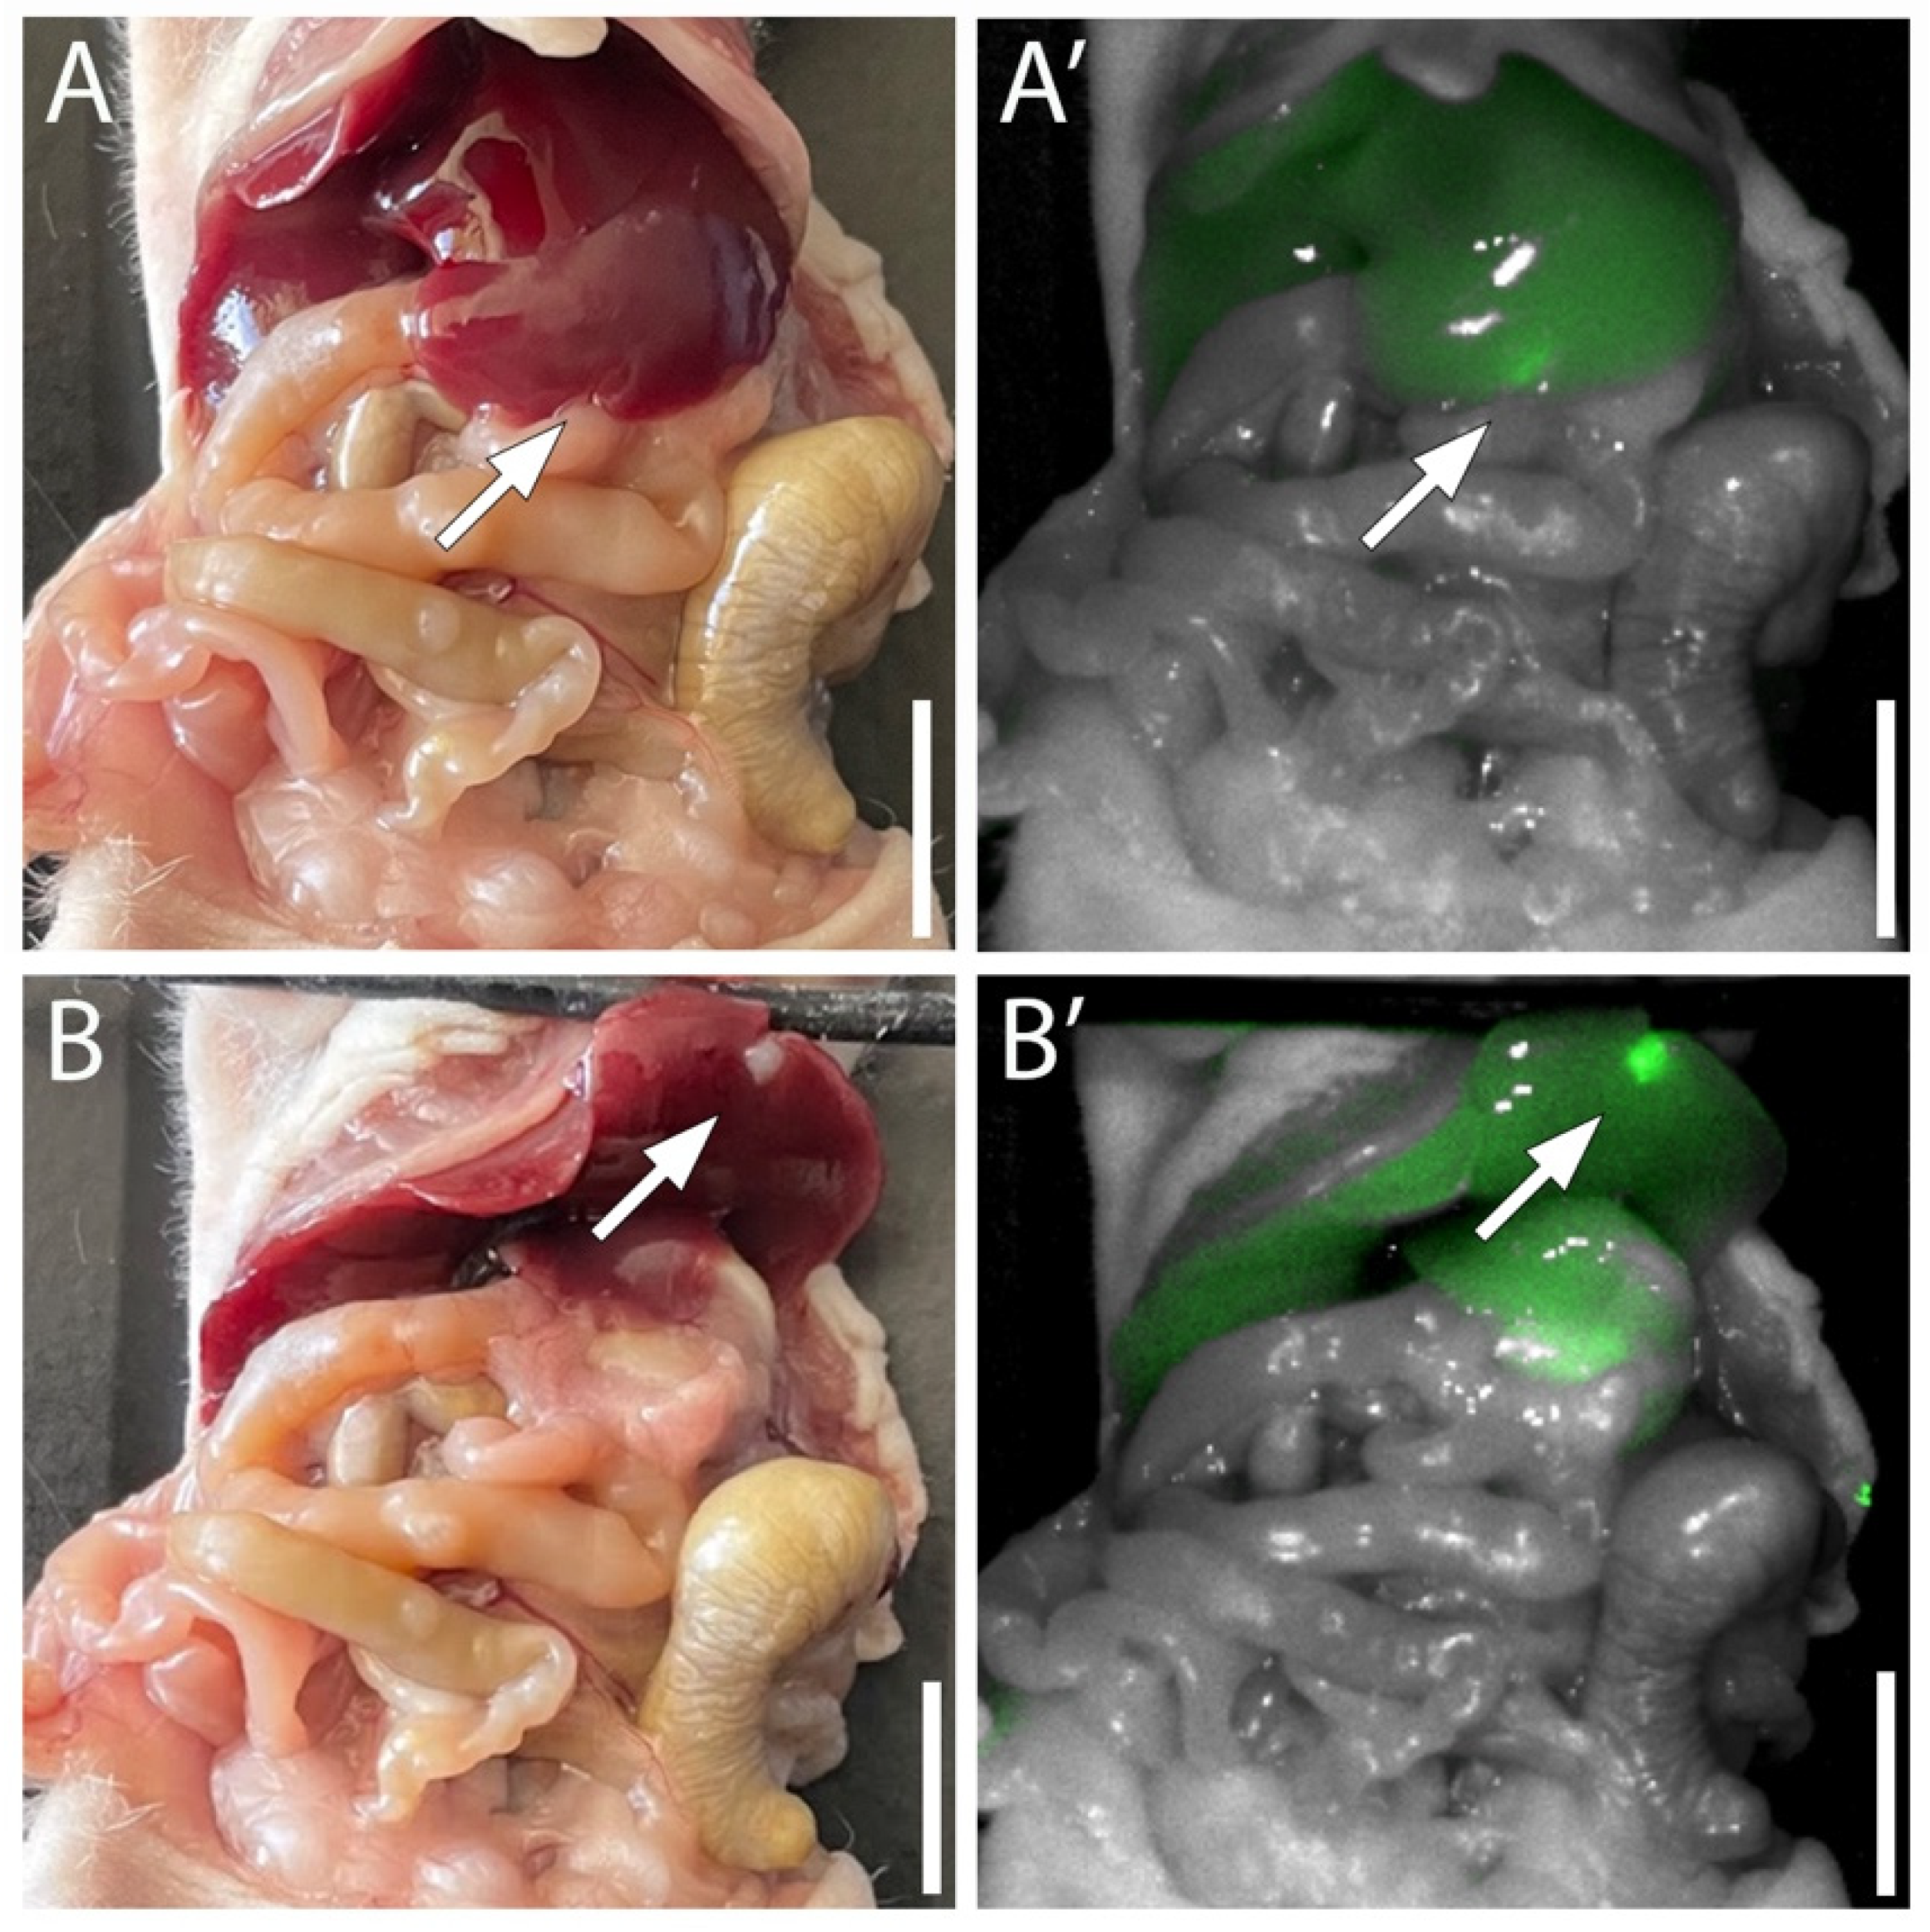

3.4. Targeting Pancreatic Cancer in the Liver with MUC5AC-IR800